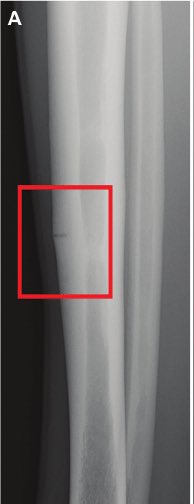

🔅طيب كيف نشخص هذه الكسور ؟!

يمكن للأطباء احيانا التشخيص من خلال الفحص البدني و التاريخ الطبي ولكن غالبًا ما تكون هناك حاجة لإجراء عمل الأشعة .

والتشخيص يتم عن طريق اشعة MRI وهي الاكثر دقة لتشخيص هذا النوع من الكسور على عكس الأشعة العادية X-Ray